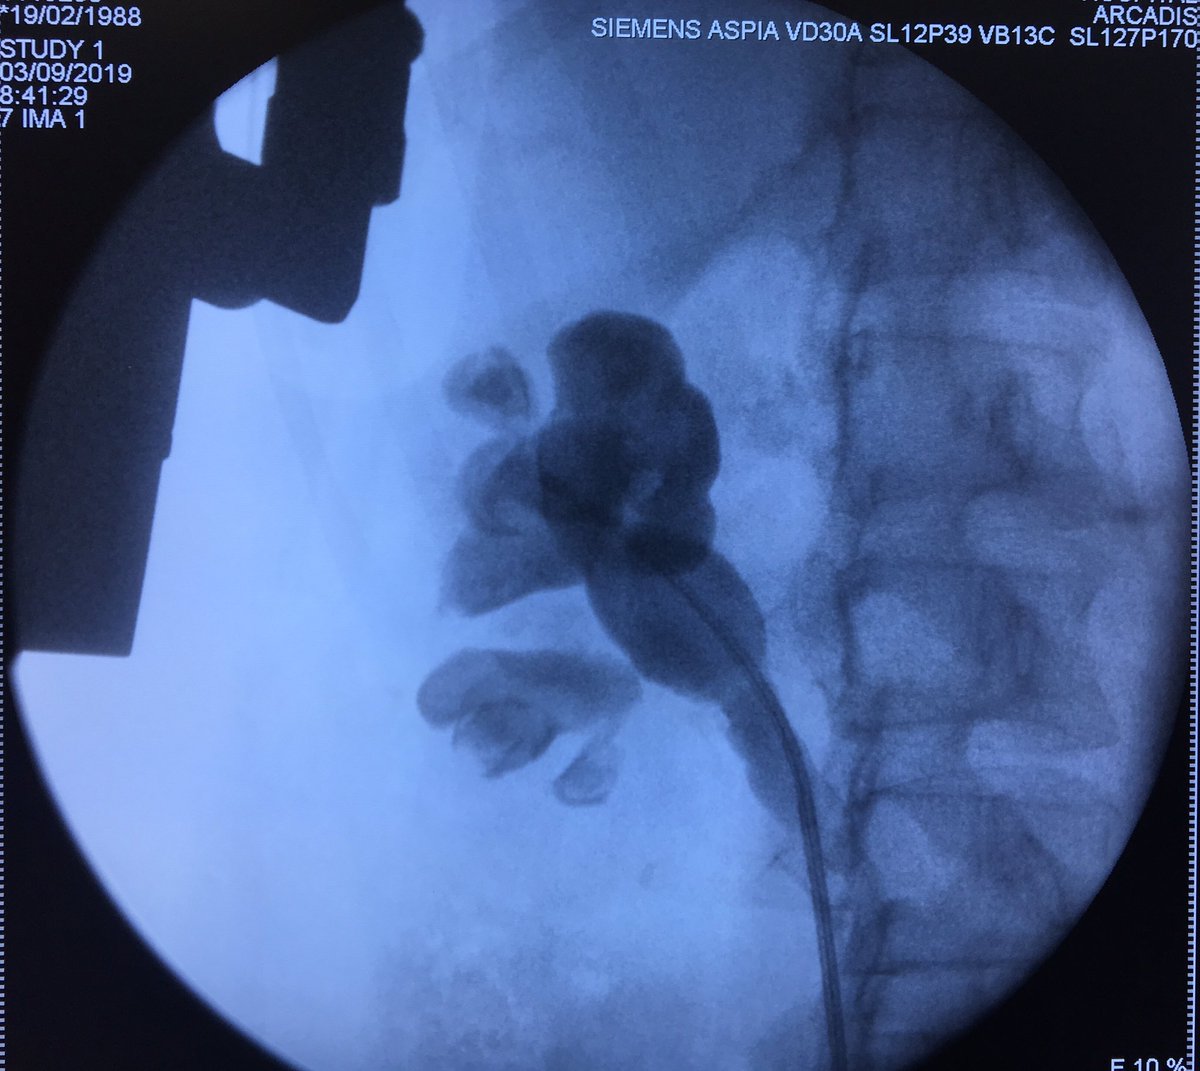

ECIRS with the Escovar-Leon Technique. Fast and accurate renal puncture! @urobraulio

#miniperc is a great option for aditional tract when flexible ureteroscope is not available for ECIRS. Triangulation with Escovar-León technique. #UroSoMe #Ilovepcnl @urobraulio @2fabiosepulveda

Two fiber laser 270 and 500 vs one hard stone... ECIRS is the way to go Thanks #suequimed #ems @urojavo @urobraulio @alexfige86 @scoffonecesare @karenmbravo @DavidCabrera88 @cescernesto @cmordin75